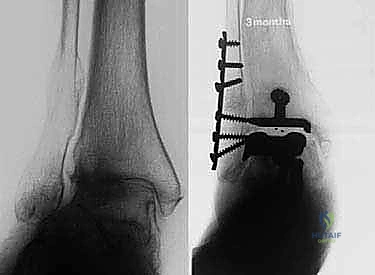

- الأشعة السينية (X-rays) بوضعية الوقوف: وهي الأداة الذهبية للتشخيص. صور الأشعة والوزن محمل على القدم (Weight-bearing X-rays) تظهر بدقة مدى تآكل الغضروف (ضيق المسافة المفصلية)، وجود نتوءات عظمية (Osteophytes)، وأي انحراف في المحور الميكانيكي للساق.

* التثبيت: هو مفصل "غير إسمنتي". يتم تغطية الأسطح المعدنية الملامسة للعظم بطبقة مسامية من التيتانيوم وهيدروكسي أباتيت (Hydroxyapatite). هذه الطبقة تشجع العظم الطبيعي للمريض على النمو داخل مسام المفصل (Bone Ingrowth)، مما يوفر تثبيتاً بيولوجياً صلباً يدوم لسنوات طويلة.